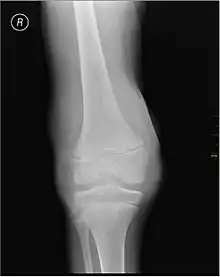

يدل النزف العضلي ونزف المفاصل (تدمي المفصل) على الهيموفيليا،[7] في حين أن نزف الجهاز الهضمي والنزيف الدماغي يكون ذات صلة باضطرابات التخثر الأخرى. وعلى الرغم من أن النزف المفصلي ليس مهددا للحياة، إلا أنه من أخطر أعراض الهيموفيليا. فقد يسبب النزيف المتكرر في محفظة المفصل تلف دائم وتشوه للمفصل، مما يؤدي إلى التهاب المفاصل المزمن والعجز. لا يحدث تلف المفصل نتيجة وجود دم في المحفظة، ولكن بسبب عملية الالتئام. عندما يتم تكسير الدم الموجود في المفصل بواسطة إنزيمات الجسم، يتم أيضا تكسير العظام في تلك المنطقة، مما يسبب الكثير من الألم للشخص المصاب بالمرض.